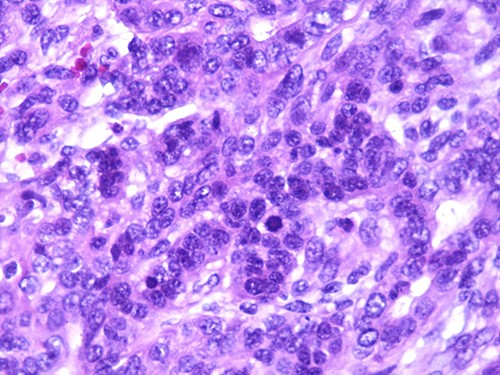

A 46-year-old woman, without clinical antecedent, presented with a tumor in the inner side of the left cheek which had rapidly grown for 3 weeks. Physical examination revealed an ulcerating mass measuring 4 × 3.5 cm, well-circumscribed, fleshly, with a white surface. There was submandibular lymphadenopathy, ranging in dimension from 1 to 1.5 cm in diameter. Magnetic resonance imaging (MRI) scan revealed the tumor of the cheek without mandibular bone infiltration or sinonasal involvement (Fig. 1). Chest computed tomography and abdominal ultrasound scan were unremarkable. An excisional biopsy was performed. Pathological examination showed a neoplastic proliferation composed of mixture of mature benign epithelial components, such as intestinal type, respiratory and squamous epithelia, and mature mesenchymal components, such as muscular tissue and cartilage (Fig. 2) and neuroglial tissue. In addition, immature and malignant tumor components were found such as small blue tumor cells resembling primitive neuroectodermal tumor (Fig. 3), adenocarcinoma and sarcoma with muscular and cartilaginous differentiation (Fig. 4). This tumor infiltrates the skeletal muscle with free margins. Immunohistochemically, epithelial components were positive for pankeratin; mesenchymal components showed desmin, myogenin and S-100 positivity and the primitive neuroectodermal tumor component was positive for NSE, CD99, GFAP, synaptophysin and focally for chromogranin. SALL4 was negative. The resected submandibular lymph nodes were devoid of malignant infiltrate. The diagnosis of TCS was established and the patient was treated by combined chemotherapy (cisplatine +5 fluorouracil) and radiation therapy. No recurrence was noted 6 months after treatment.

Photomicrograph of carcinomatous component (magnification at ×400).